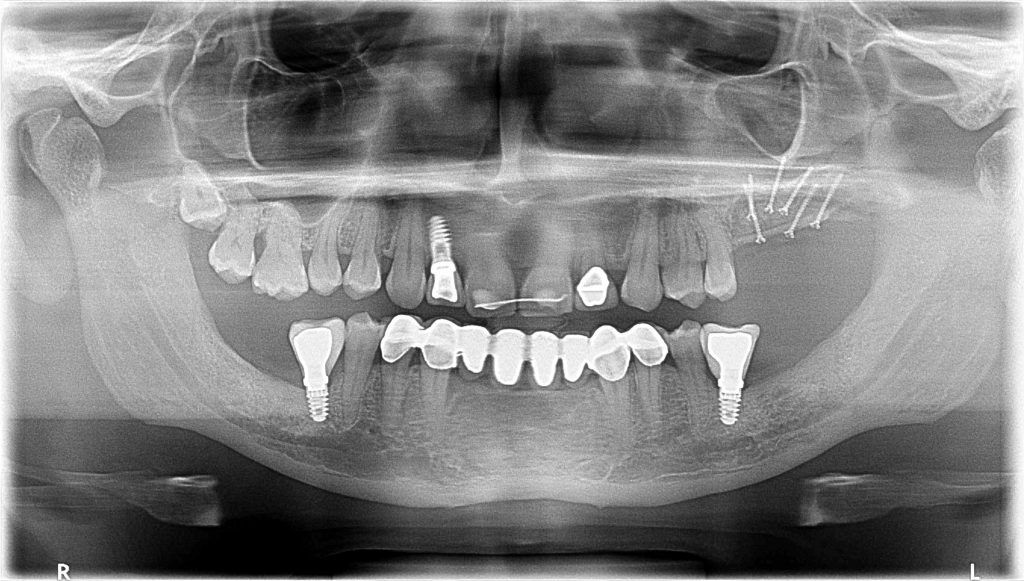

Here you will be able to see how we manage bone atrophies in different areas of the oral cavity.

From an augmentation in the posterior mandible to an augmentation in the anterior region of the mandible to another one in the anterior area of the maxilla.

The longer and deeper the defect is, the more difficult the procedure is.

This is also one of the biggest advantages of using autogenous bone and this reconstructive model. We are able to combine different procedures, such as:

- Sinus lift + Bone augmentation

- Implant Placement + Horizontal Augmentation

- Nerve Lateralization + Bone Augmentation

- Bone Augmentation + Soft Tissue Augmentation

- Canine Management in Oral Implantology: Extraction + Implant Placement + Graft